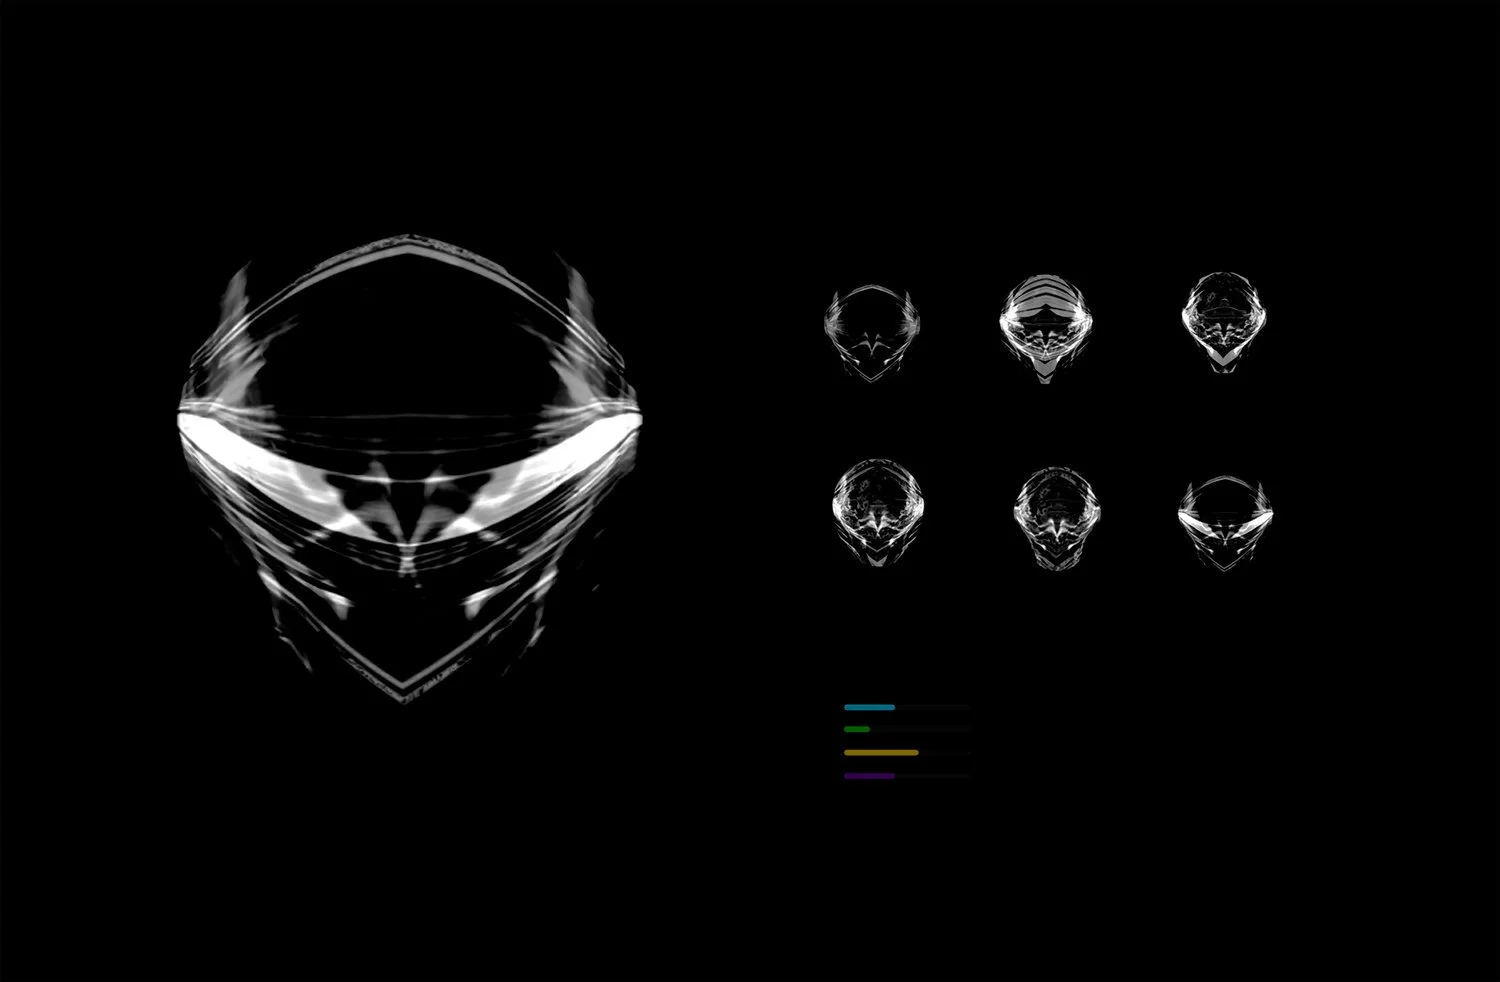

MRI 17910, Jakob Dwight, 2013, Digital print /Duratrans backlit film for lightbox

Astrocytoma, Jakob Dwight, 2014-2017, digital print

Astrocytoma, Jakob Dwight, 2012-2014, digital print

Avatar Selection Screen, Jakob Dwight, 2016, digital print

MRI, Jakob Dwight, 2013, digital print